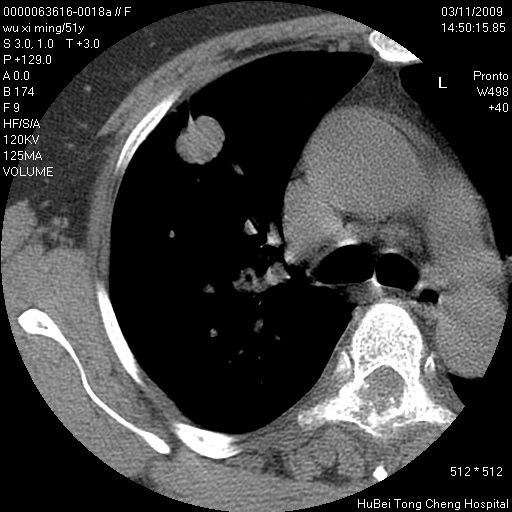

患者 女,51岁。因“胆囊炎,胆囊结石”,行常规术前胸部x线检查发现:右上肺结节病灶,建议行进一步检查。患者无咳嗽、咳痰及咯血等呼吸道症状,近期出现背部疼痛不适。

胸部ct轴位平扫(层厚10mm,螺距1.5,重建间隔10mm;部分层面:层厚3mm,螺距1.0,重建间隔3mm),图像如下:

右肺周围型肺癌伴肺内转移信胸椎转移

1、周围型肺癌。(毛刺正、血管束集征,分叶。)

集束征,胸膜牽拉征,毛刺,淺分葉高度提示ca.

右肺周围型肺癌伴肺内转移及胸椎转移。已无手术机会。